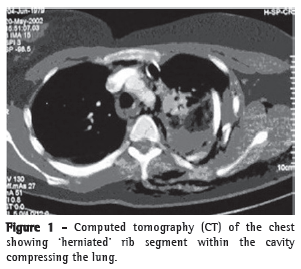

A 32-year-old female patient suffered an automobile accident which resulted in left hemopneumothorax, left pulmonary contusion and double fractures extending from the third to the eighth left costal arches, as seen on chest X-rays and computed tomography scans of the chest (Figures 1 and 2). Tomography of the skull, cervical spine, abdomen, and pelvis, were normal, as were the electrocardiogram and echocardiogram, as well as the results of tests for muscle enzymes and markers of myocardial necrosis. Water-sealed thoracic drainage was performed, and the implantation of an epidural catheter was inserted in order to provide continuous analgesia using an infusion pump. The patient presented significant chest deformation and pain, despite high doses of painkillers. It was expected that this profile, unless surgically treated, would evolve to complex deformation of the chest wall, with possible respiratory impairment. The patient did not require mechanical ventilation. In view of this clinical profile, surgical treatment was indicated in order to stabilize the fractures. The procedure was performed using left posterior lateral thoracotomy. We found double fractures extending from the third to the eighth left costal arches, with complete rupture of various intercostal pedicles, herniation, and impaction of the fractured segment (six arches) within the pleural cavity, with significant compression of the pulmonary parenchyma (traumatic thoracoplasty). We performed reduction of the fractures and fixation of the ribs with number 5 steel wires, perforating the extremities of the ribs with a nº 2 drill, passing the steel wire from one rib segment to another, and tying it. A chest tube was inserted and left in place until the third day. The patient evolved to excellent pain control and improved respiratory dynamics. Postoperative X-rays and tomography scans confirmed the favorable result of the surgical treatment (Figure 3).

Closed chest trauma is an important cause of morbidity and mortality, principally when accompanied by flail chest. It occurs when there are multiple fractures of the chest cavity, more specifically when we observe fractures of three or more ribs, at two or more points, together with fluctuation, paradoxical breathing, or both.(3) Traumatic thoracoplasty can be defined as a condition in which the fractured segment migrates into the chest and becomes lodged within the segments of the fixed costal arches, causing impaction of this segment within the pleural cavity. This causes intractable pain (permanent traction of intercostal nerves) and compresses the pulmonary parenchyma, considerably worsening the clinical profile of the patient. Severe flail chest is associated with respiratory failure, due to the retention of secretions, atelectasis, pneumonia, and, later, restricted mobility of the chest cavity.(2) Thoracic instability can be efficiently treated with analgesia, preferably epidural, and physical therapy, with proper secretion mobilization.